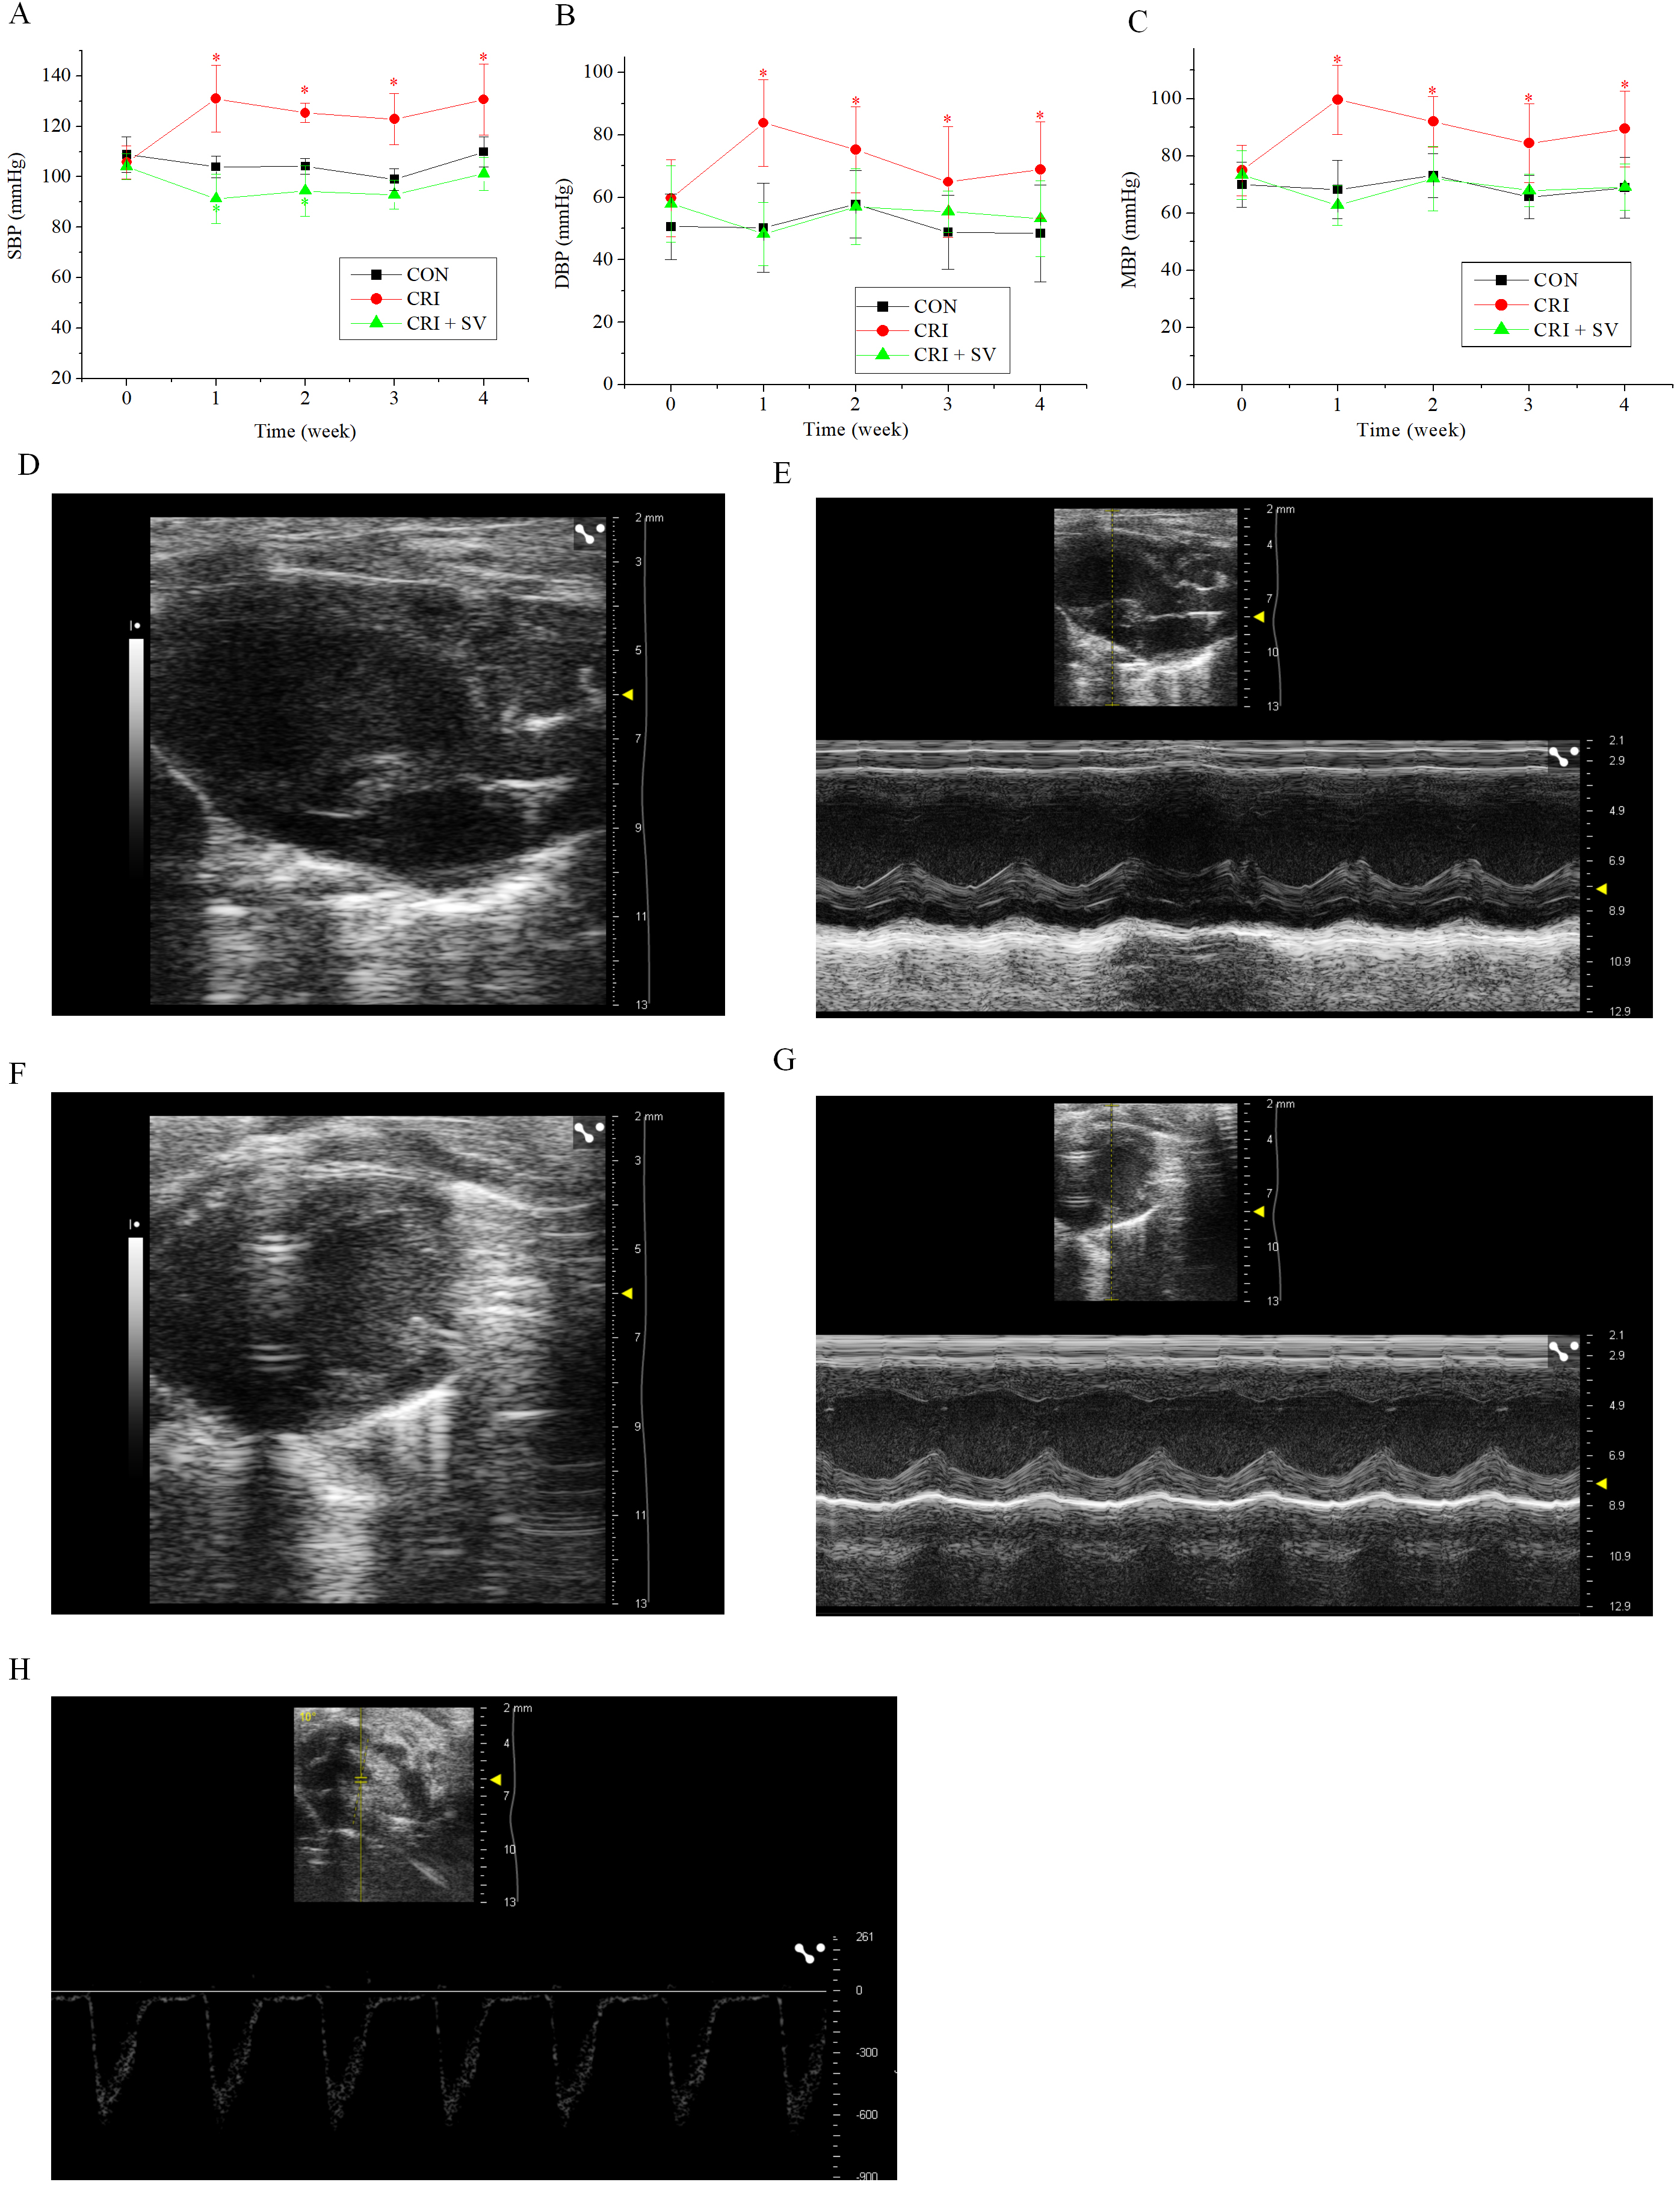

To study the cardiotoxicity caused by crizotinib, the blood pressure (BP) of mice after crizotinib administration was measured. The SBP, DBP and MBP were significantly higher following crizotinib treatment for 1 week (n = 10, SBP, p = 0.000; DBP, p = 0.000; MBP, p = 0.000), and remained significantly elevated at 4 weeks after treatment (n = 10, SBP, p = 0.000; DBP, p = 0.009; MBP, p = 0.001) when compared to the control group (Fig. 1A–C). HE and Masson staining was performed on ventricular muscle tissue obtained from mice 4 weeks after crizotinib use. No significant changes in myocardial tissue structure nor significant myocardial fibrosis was observed in control and crizotinib group mice (n = 5) (Fig. 1D,E). We also recorded the characteristics of epicardial electrical conduction of mice using mapping. Fig. 1F is a representative epicardial electrical mapping of LV. The calculated CV (n = 5, p = 0.553), absolute inhomogeneity (n = 5, p = 0.365), and inhomogeneity index (n = 5, p = 0.404) of LV were not significantly different between the control and crizotinib groups (Fig. 1G–I). A representative epicardial electrical mapping of RV is shown in Fig. 1J. The calculated CV (n = 5, p = 0.532), absolute inhomogeneity (n = 5, p = 0.702), and inhomogeneity index (n = 5, p = 0.926) of RV was also found to not change significantly in control and crizotinib groups (Fig. 1K–M).

Fig. 1.Effect of crizotinib on BP, myocardial pathology, and electrical

conduction characteristics in control and crizotinib group mice. (A) Effects of

crizotinib on SBP. (B) Effects of crizotinib on DBP. (C) Effects of crizotinib on

MBP. (D) Typical sample of HE staining in control and crizotinib group. (E)

Typical sample of Masson staining in control and crizotinib group. (F)

Representative epicardial electrical mapping of recorded LV. (G) CV of LV. (H)

Absolute inhomogeneity of LV. (I) Inhomogeneity index of LV. (J) Representative

epicardial electrical mapping recording of RV. (K) CV of RV. (L) Absolute

inhomogeneity of RV. (M) Inhomogeneity index of RV. *p